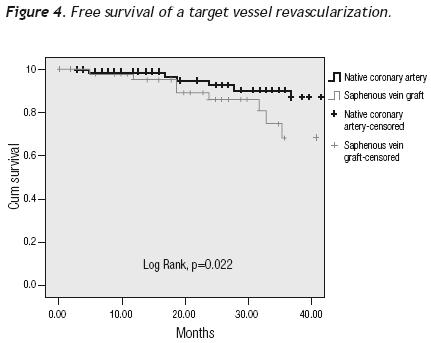

A tendency towards a lower MACE incidence was observed in group 2 at 3 years (34.6% vs. 23.0%, p = 0.075). The use of bare–metal stents or DES did not modify the incidence of accumulated MACE. The MACE–free survival by the Kaplan–Meier analysis was 65.0% in the SVG group and 89.1% in the native vessels group (p = 0.024). TVR–free survival was 74.8% and 92.8%, respectively (p = 0.022; Figures 3 and 4). Risk estimation for TVR with the use of DES revealed a reducing–effect tendency, with OR 0.28 (IC 95%, 0.06–1.31, p = 0.09). The TVR–free survival at 36 months in the whole population with the use of DES was 94.1%, compared to 89.8% with bare metal stents (p = 0.64).

In our study, the MACE–free and TVR–free survival at 36 months was higher in the PCI of native vessels group than in the PCI of venous grafts group. The use of DES did not modify the TRV rate during the 3 years of follow–up in the population as a whole.

In this study, we compare the results of intervening venous grafts versus native arteries in patients with previous coronary artery bypass surgery. Results show a higher MACE rate during the in–hospital phase for group 1 (venous grafts), and a better MACE–free and TVR–free survival for native vessel PCI. To get definite conclusions, it will be necessary to perform a randomized prospective study using distal embolic protection devices, as well as direct stenting and DES in both groups.